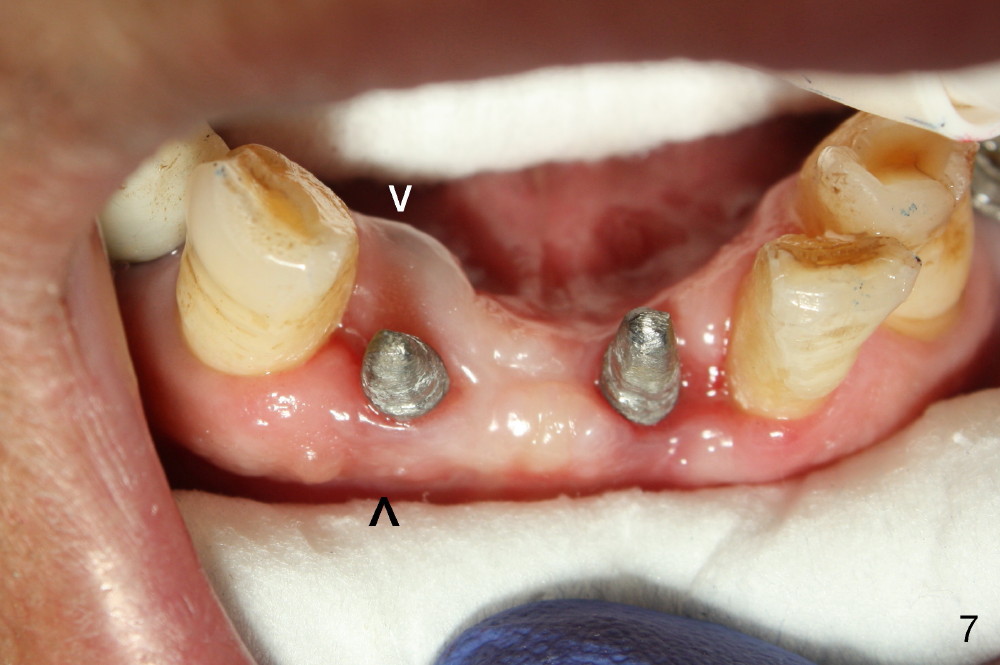

Fig.7 shows these two one piece implants immediately prior to cementation of the FPD (Fig.8). They are much more parallel to each other after prep, as compared to Fig.6. Fig.9 shows apparent bone growth around #24 implant (at the crest) 6,9 months post cementation and surgery, respectively. Orthodontic treatment will incorporate the fixed partial denture. Fig.10 shows that bone grows coronally (arrow) to cover 3 threads (from #6 thread to #3) at the site of #24 one year after functioning. There is mild buccal gingival infection involving #26 retainer. Preop CBCT is reviewed to determine whether it is related to potential thread exposure. It appears that at the sites of #24 (Fig.13,14) and 26 (Fig.11,12), 2.5 mm implant is more appropriate for the narrow ridge than 3.0 mm one. In fact, periimplantitis develops at #26 two years of absence of perio maintenance (because of atrial fibrillation with blood thinner; Fig.15, 3 years 7 months post cementation). Periimplantitis persists 4.5 months later. Although water pik is purchased, it is not used often because of low blowing force. If needed, remove the FPD atraumatically. Unwind the implant, clean the coronal threads with Titanium brush or remove the exposed threads and replant the implant with bone graft.